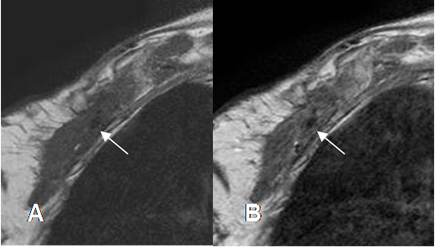

Fig 9B. Cambios por radioTx.

A: RM sagital en T1 simple y B: RM sagital en T1 con contraste. Igual paciente anterior. No se pueden identificar las raíces del plejo, las cuales están rodeadas por tejido inflamatorio, que realza con el contraste, secundario a cambios por radioTx.

Fig 9 C. Cambios post radioTx.

A: RM axial simple y B: RM axial con contraste. Igual paciente anterior. Alteración de la pared torácica anterior, por cambios Qx. Reemplazo de la grasa que rodea las raíces del plejo braquial, la cual realza con el contraste, por fibrosis secundaria.